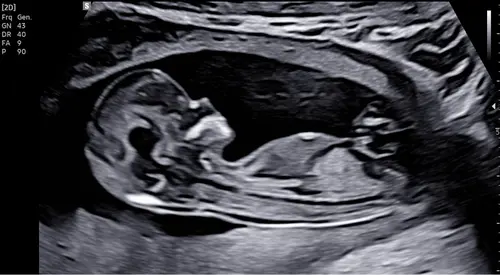

Iemand een idee? Ik heb echt geen idee waar ik moet kijken ☺️

Ik denk een jongen

Ja denk ook jongen! Je ziet iets uitsteken